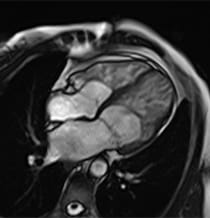

Image of LVNC Heart.

Image of a heart with left ventricular non-compaction cardiomyopathy.

What Is Left Ventricular Non-Compaction Cardiomyopathy (LVNC)?

In LVNC, muscle in the heart's left ventricle — one of two lower chambers — becomes sponge-like, with extra space between the muscle tissues. These heart muscle changes can affect how the left chamber pumps blood and can allow blood clots to form in the chamber.